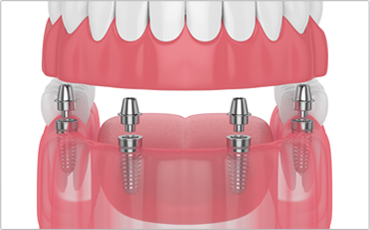

OSCAR All-on-X 임플란트

기존 틀니에 디지털을 더한 전악 회복 프로젝트!

오스카55플란트치과 OSCAR All-on-4 임플란트는

적은 식립으로 전체 임플란트가 가능합니다.

치아가 하나도 없는 경우에도 4개의

소수 임플란트를 식립하여 전체 치아를 수복합니다.

소수 임플란트 식립 (4개)

탈착하지 않아도 되는 편리함

경제적인 비용